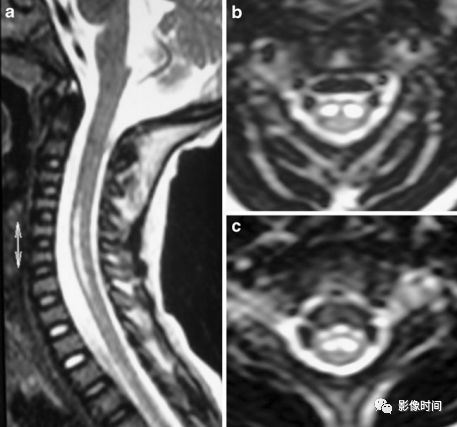

急性横贯性脊髓炎(Acute transverse myelitis,ATM):是一种脊髓的炎性疾病,原因不明,进展迅速,大致运动、感觉和自主神经功能障碍,10-19 岁和 30-39 岁之间多见,无性别差异或家族倾向,通常没有神经系统异常的既往史。

轴位占脊髓直径 2/3,长度:3-4 个椎体长度

T2WI显示脊髓内长节段高信号,范围超过脊髓直径2/3,斑片状明显强化

T2WI双侧灰质前角对称结节状高信号,似「鹰眼」

轴位「鹰眼征」

-

矢状位「铅笔征」

脊髓前动脉梗死导致双侧灰质前角梗死(鹰眼征),矢状位呈线样,DWI 提示细胞毒性水肿